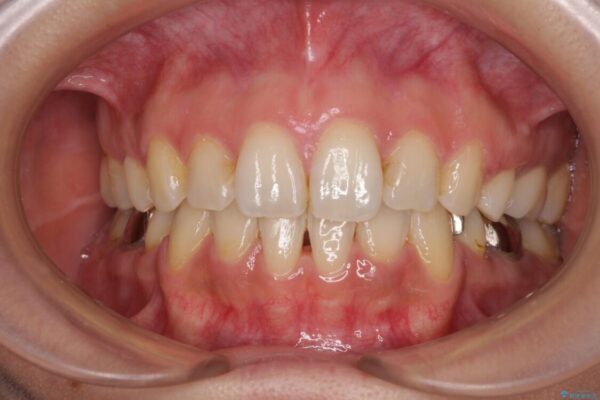

治療後について

表側のワイヤー矯正に比べると治療期間は長く、費用も高額となりますが、どうしても目立たせたくないという方にはお勧めの抜歯矯正です。

治療後

• デコボコと口元の突出感 ハーフリンガルでの抜歯矯正 治療後画像